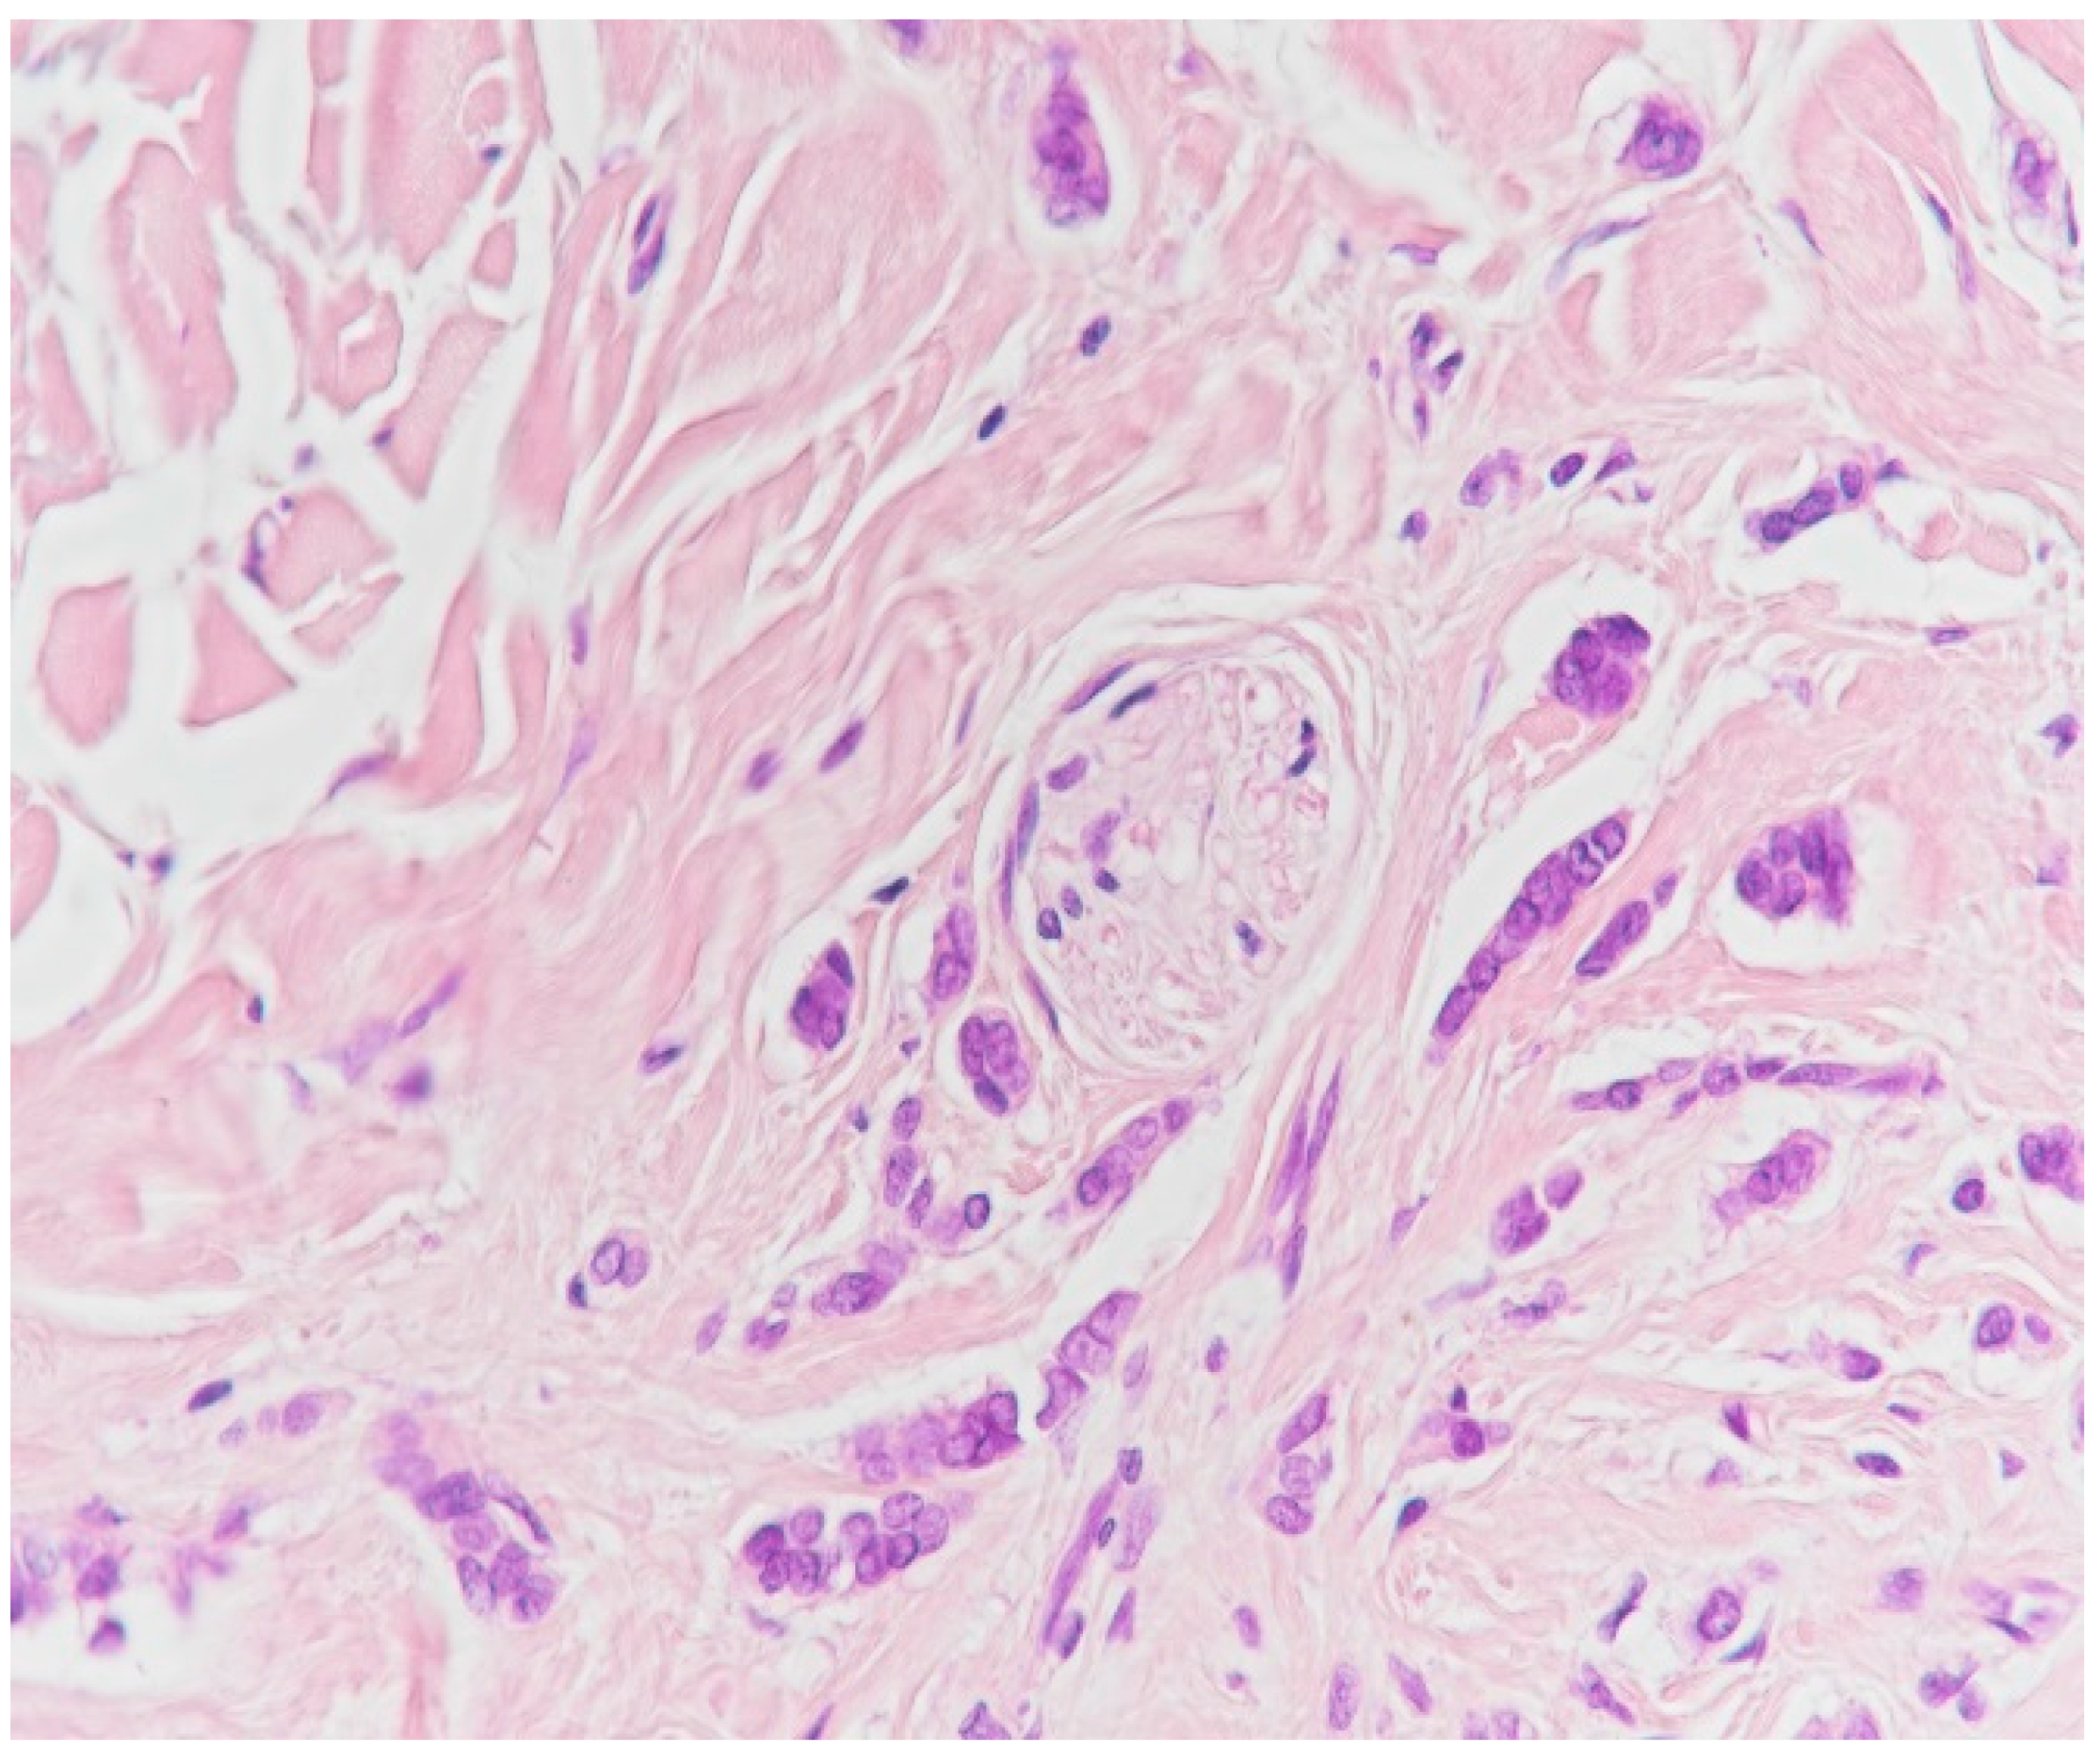

2. Case Presentation